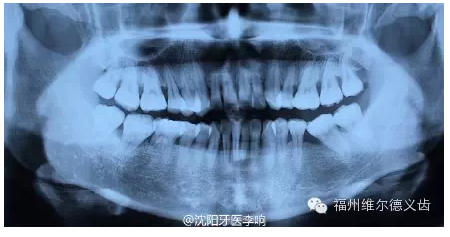

這時候又沒處理,齲齒向深層的神經(jīng)侵襲,表現(xiàn)為牙痛的不行,這時候的治療叫根管治療,后牙的現(xiàn)代根管治療技術(shù)通常要兩千元左右,而且這不算完,大多數(shù)牙齒在根管治療之后需要做一個牙冠保護起來,就是常說的烤瓷牙了,這烤瓷牙便宜的要幾百元,貴的要七八千元,這一套都下來少則兩三千,多則上萬,這時候普通人承受起來普遍比較吃力了。

QQ圖片20150725100208.png